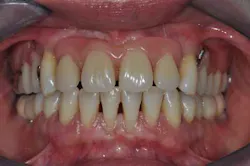

Figs. 8a, b, c, and d: Final results